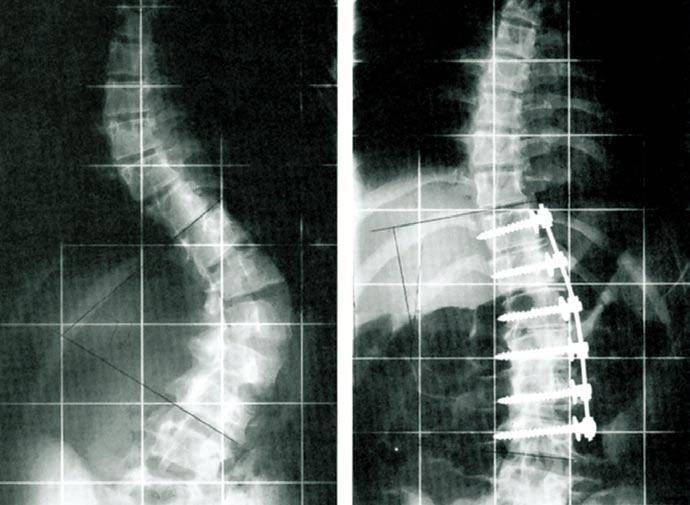

Treten nach mehreren Jahren plötzlich Beschwerden auf, sollten Patienten in jedem Fall einen Facharzt aufsuchen. Manchmal ergeben sich aus der Versteifung der Wirbelsäule Ausgleichsbelastungen. Dies bedeutet, dass der Patient die eingeschränkte Flexibilität der Wirbelsäule durch Schonung oder eine veränderte Haltung ausgleichen möchte.. Postoperative Betreuung nach Wirbelsäulen-OP: Tipps & Ratschläge . Du hast eine Operation an deiner Wirbelsäule hinter dir und überlegst, was jetzt zu tun ist? Es ist völlig normal, dass du nach der OP Schmerzen und Beschwerden hast. Es kann Wochen oder sogar Monate dauern, bis du dich wieder vollständig erholt hast.